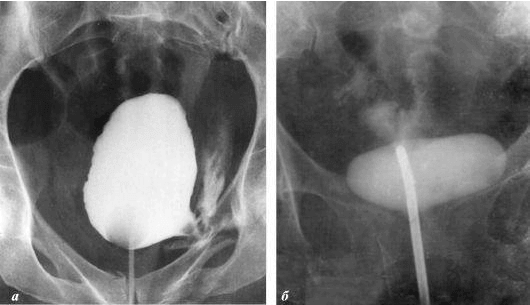

Je veux vous montrer quelques photos pour montrer ce qui se passe dans le système génito-urinaire et d'autres organes d'un homme qui n'a pas de relations sexuelles.

interesting image

À quoi ressemble l'inflammation de la prostate causée par la stagnation du sperme (lorsque les testicules ne sont pas vidés). L'inflammation constante conduit d'abord à l'adénome de la prostate, puis au cancer. C'est une conséquence inévitable de la prostatite, c'est pourquoi on l'appelle la «maladie de l'ancienne génération».